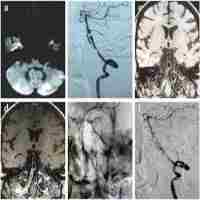

| Abstract | Symptomatic intracranial atherosclerotic disease (sICAD) remains a challenging disorder in the neurovascular field. Despite best medical treatment (BMT), the recurrence rate for stroke remains high in patients with intracranial high-grade stenosis (>70-99%). Furthermore, two large randomized trials (SAMMPRIS and VISSIT) failed to prove the efficacy of percutaneous transluminal angioplasty and stenting (PTAS) in patients with sICAD. Drug-coated balloon percutaneous transluminal angioplasty (DCB-PTA) represents an alternative treatment modality with therapeutic benefits for interventional cardiology. However, there are very few articles in the existing literature that relate to the use of DCB-PTA in sICAD patients. Here, we aimed to review the rationale underlying the use of DCB-PTA in sICAD patients and summarize recent developments in the neurovascular field. |